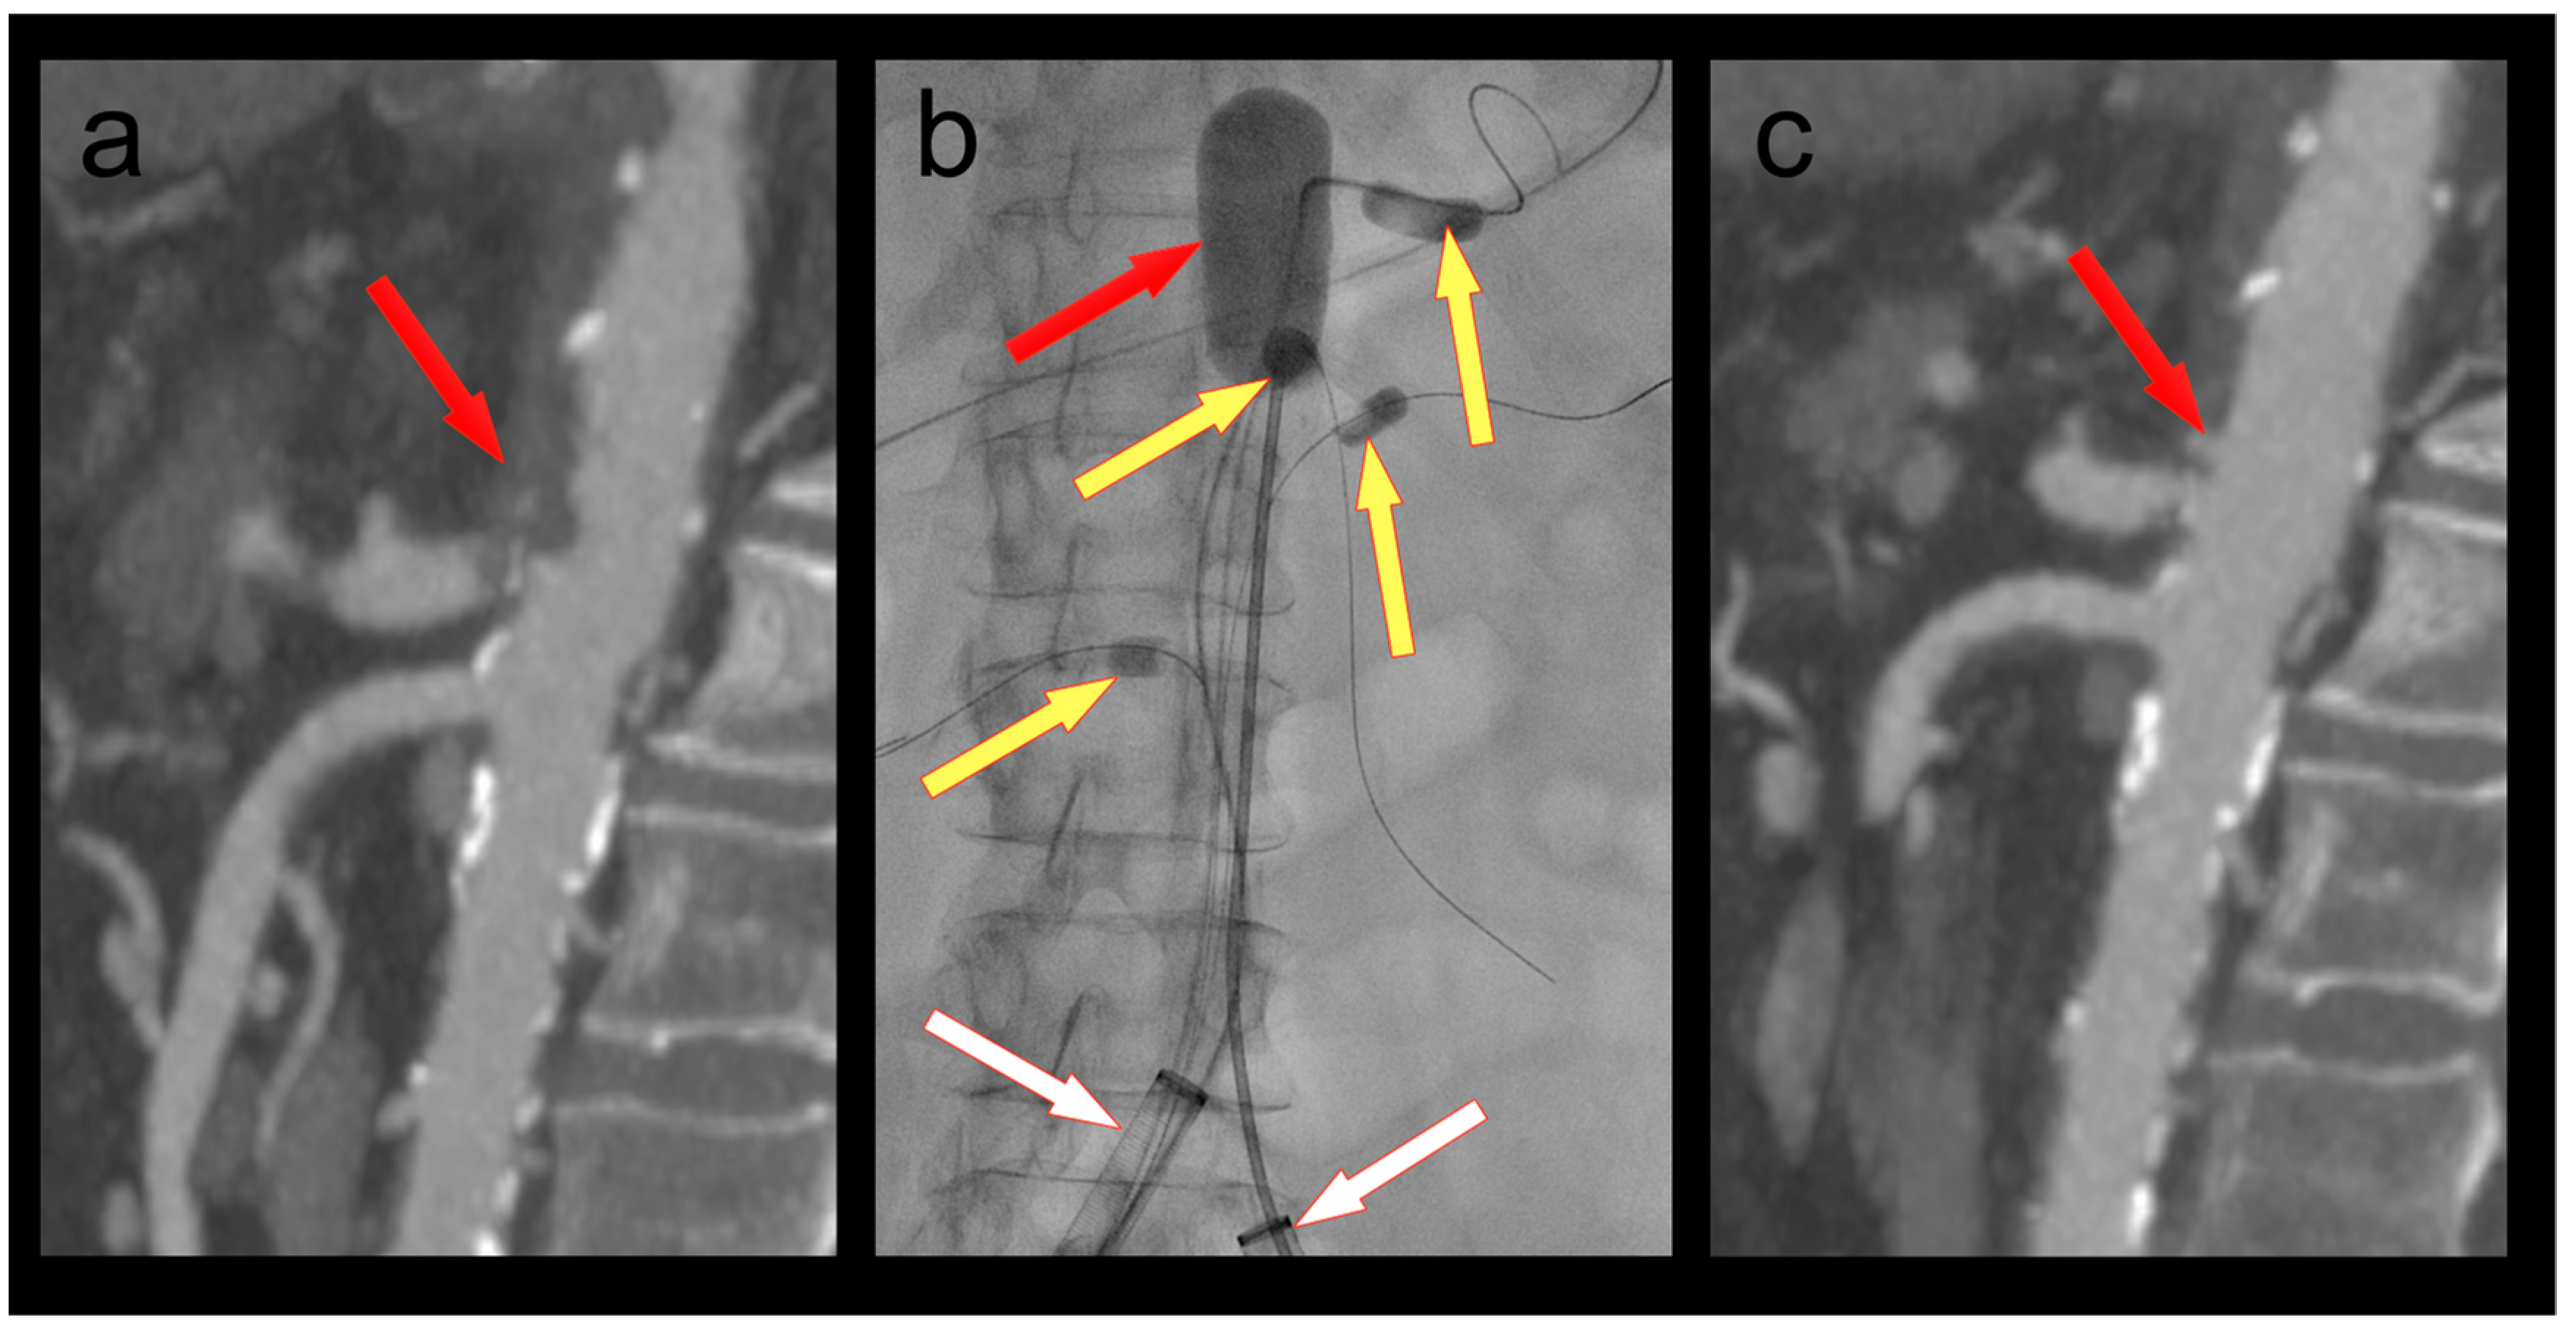

A 61-year-old female patient was admitted because of respiratory failure due to bilateral COVID-19 pneumonia. A CT angiography detected several appositional thrombi throughout the thoracoabdominal aorta, the biggest of which was located at the origin of the coeliac trunk (Figure 2). Another scan two days later showed progression of the thrombi in spite of therapeutic heparin. The coeliac trunk was nearly occluded, and the right hepatic artery was completely occluded. Furthermore, the patient had acute cholecystitis. To avoid further embolization, we decided to thrombectomize the aorta and the origin of the coeliac trunk. The coeliac trunk, superior mesenteric artery, and both renal arteries were protected by OTW Fogarty® catheters, while the hypogastric arteries were protected by advancing the large-bore sheaths into the common iliac arteries. Thrombectomy of the entire aorta into the large sheaths was performed using an 8–22F Fogarty® occlusion catheter (Figure 2). The 5.5F Fogarty catheter that blocked the coeliac trunk was then used to thrombectomize its origin. There was no relevant residual thrombus in the aorta or the coeliac trunk on completion angiography (Figure 2). No further thrombotic complications were seen under therapeutic anticoagulation, and the patient was discharged home after several months in the hospital.

Figure 2. (a) Thrombus in the aorta and in the origin of the coeliac trunk (red arrow); (b) thrombectomy (red arrow) of the thoracoabdominal aorta under balloon protection of the coeliac trunk, superior mesenteric artery, and both renal arteries (yellow arrows). The large-bore sheaths are occlusive in both common iliac arteries (white arrows); (c) Postoperative CT scan with no residual thrombus in the aorta or the coeliac trunk (red arrow).